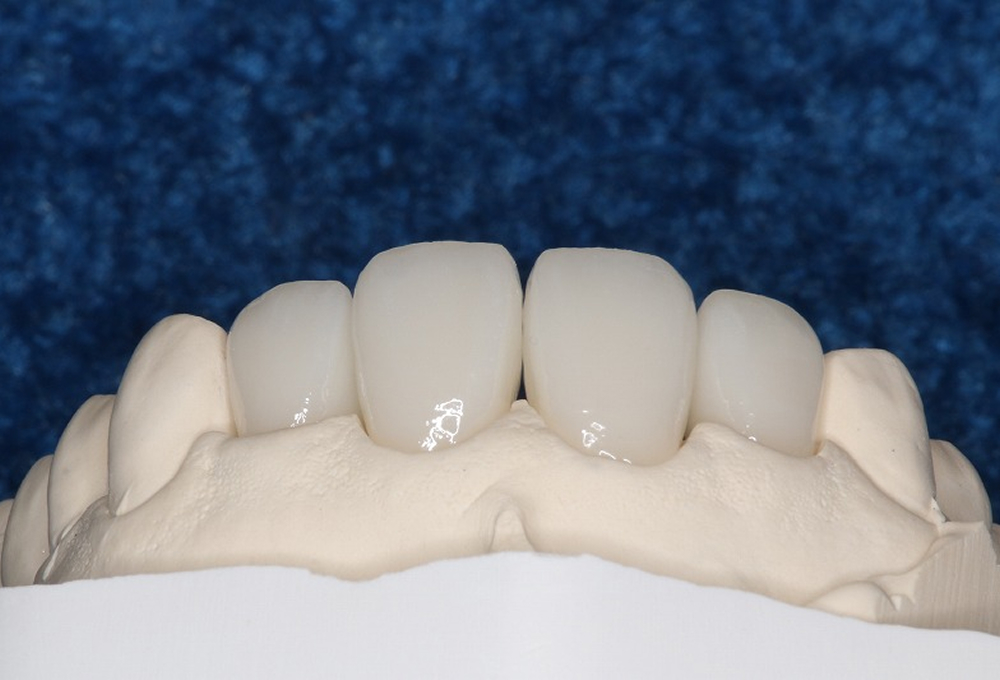

③オールセラミック

⑤ホワイトニング後 オールセラミック作製